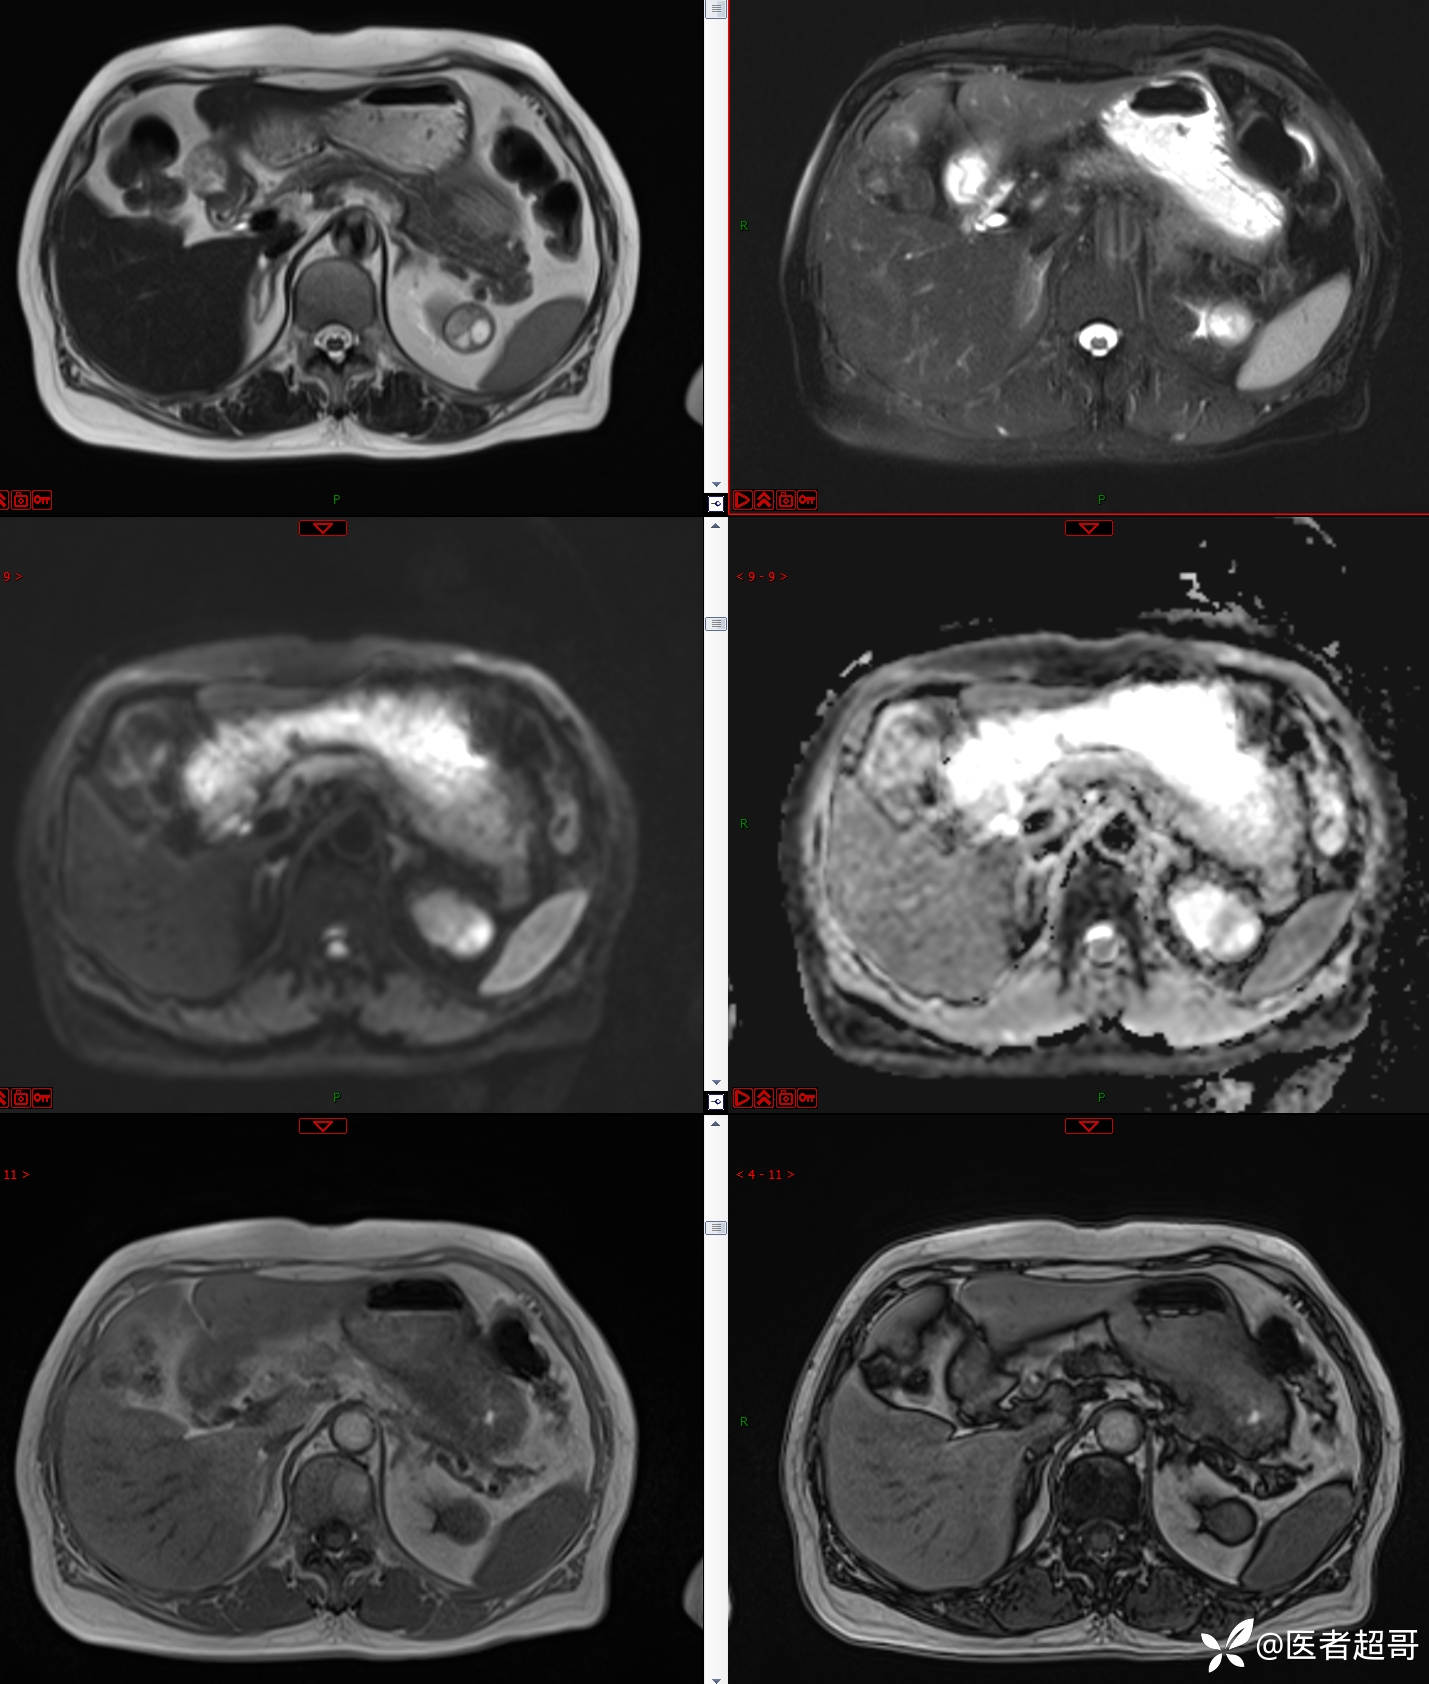

左肾占位2个月就诊,有病理,请分析!

主 诉:查体发现左肾占位2月。

现病史:患者自述2月前于镇中心卫生院行腹部超声发现:左肾实性占位。患者无尿频尿急尿痛,无发热寒战,无恶心呕吐。未行特殊治疗。现患者为求进一步诊治,就诊我院,门诊以“肾肿物”为诊断收入院,患者自发病以来,神志清,精神可,饮食可,睡眠一般,大便正常,体重未见明显改变。